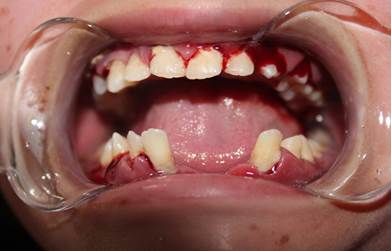

En el aspecto odontológico se evidencia cara redonda, cejas y pestañas escasas y finas, oreja grande y de implantación baja, nariz pequeña casi sin tabique nasal, labios finos y delicados, boca alargada, macroglosia, prognatismo, diastema amplio en la parte anterior de 2 centímetros de longitud, pérdida de pieza dental #31 (Figura 9). Presenta cálculo supragingival, hipertrofia generalizada de las encías, bolsas periodontales entre 5 y 6 m.m. por tanto, existe sangrado generalizado al sondaje y la palpación.  No hay presencia de caries (Figura 10).

Figura 10. Enfermedad periodontal, sangrado gingival, hipertrofia gingival

En la radiografía panorámica se evidencia los cuatro terceros molares, un supernumerario compatible por su forma y posición con canino inferior. La altura de hueso maxilar y mandibular es reducida y las piezas dentales son pequeñas. Por lo cual, existe movilidad grado dos especialmente de piezas anteriores tanto superiores como inferiores (Figura 11).

Al inicio del tratamiento, hace 3 años; se realiza remoción de cálculo y profilaxis semanales con cavitron, cepillos, pasta fluorada y clorhexidina para reducir la inflamación gingival. Luego de este tiempo se ha logrado eliminar todo el cálculo y la movilidad dentaria se mantiene. No hay presencia de caries, pero la inflamación generalizada de la encía no ha disminuido y sigue sangrando a la palpación y manipulación. Con el tratamiento preventivo se evita que haya caries y que pierda piezas dentales por problemas periodontales en lo posterior, el momento que pierda alguna pieza dental, la recesión ósea hará que vaya perdiendo más piezas y no haya la posibilidad de colocar algún tipo de prótesis.